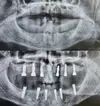

Fotoğraflar